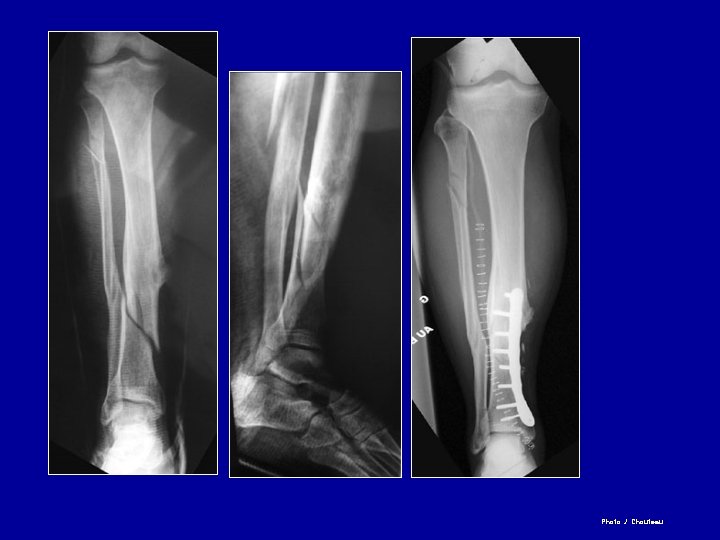

Ostéosynthèse du tibia par plaque vissée Plaque sur la corticale externe ou interne

Photo J. Chouteau